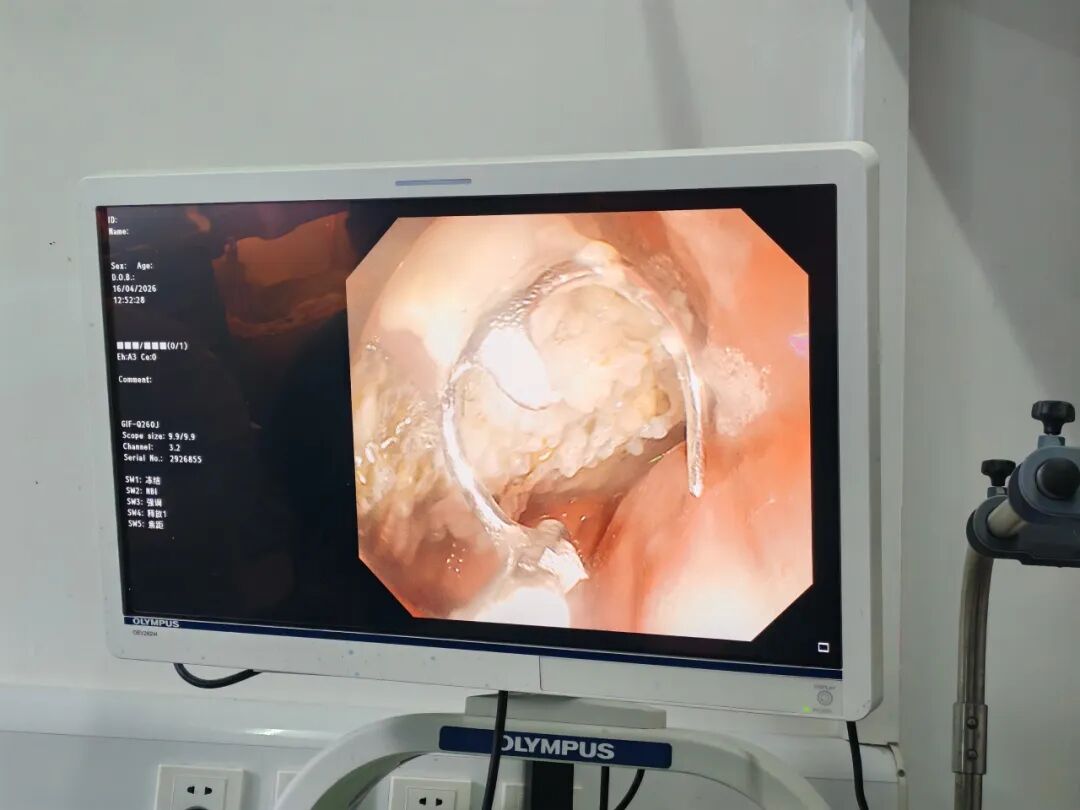

胃镜下一路直播——只见那假牙正躺在胃里面的食物中间,悠哉悠哉地“泡温泉”。

好家伙!这假牙直径3-4厘米,四枚金属爪锋利如钩,活像一只微型“金刚狼”,张牙舞爪地横卧在胃里“耀武扬威”。

镜头一:胃镜进入。屏幕上,假牙在食物和胃酸中若隐若现,金属爪随着胃蠕动一颤一颤,仿佛随时会“扎”下去。

镜头二:第一次尝试。圈套器缓缓靠近,医生屏住呼吸,试图套住假牙最稳定的桥体部分。但假牙表面湿滑,圈套器滑脱——金属爪弹向胃壁,险些在黏膜上划出一道血痕。

镜头三:精准锁定。用异物钳配合圈套器,医护协作,为防止划伤食管,两人反复尝试从不同角度先夹住假牙一侧,再慢慢往外一拖。

当假牙通过贲门时,所有人都捏了一把汗。那四枚金属爪紧贴着食管壁,稍有不慎就会造成损伤!